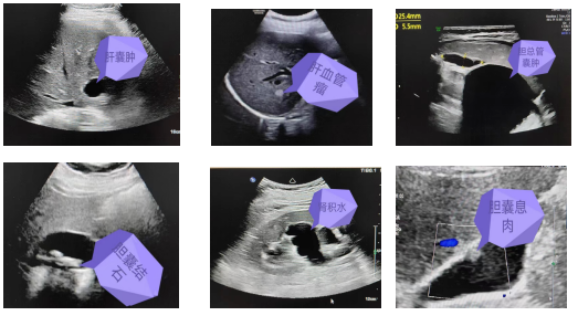

通過彩超檢查可以發(fā)現(xiàn)臟器的形態(tài)大小,有無占位性病變等。常見疾病如肝囊腫、肝血管瘤、膽總管囊腫、膽石癥、膽囊息肉、膽囊炎、肝臟脂肪變性、多脾癥、腎積水、腎結(jié)石、膀胱炎等。部分常見疾病超聲圖像如下: